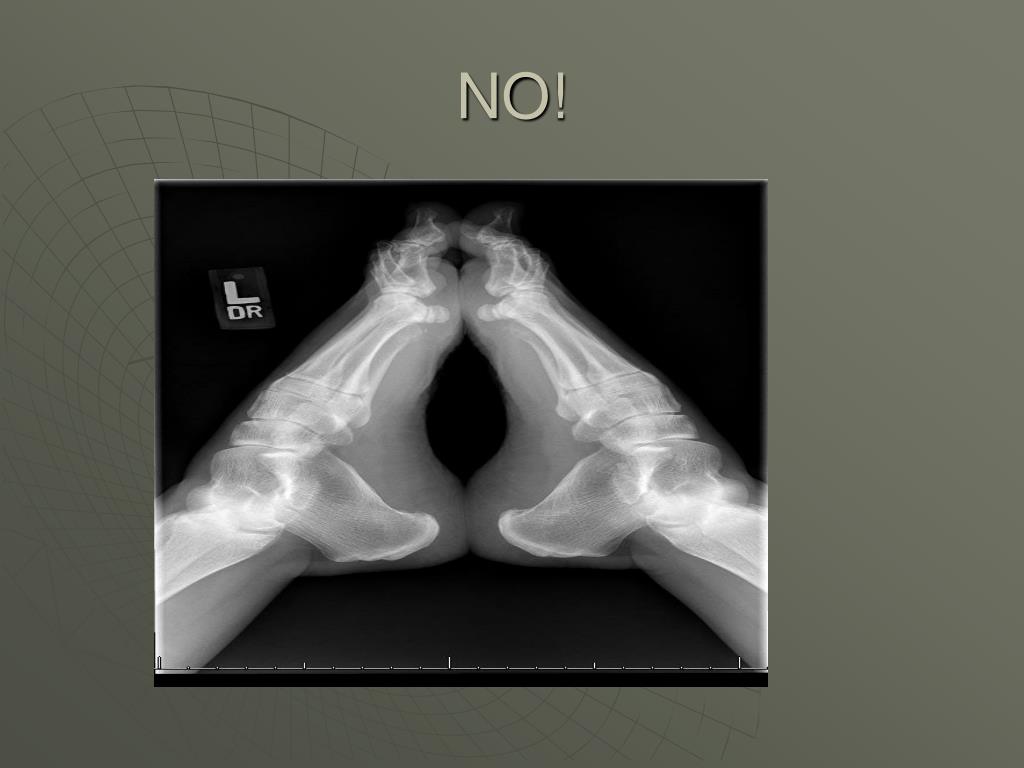

32. NO!